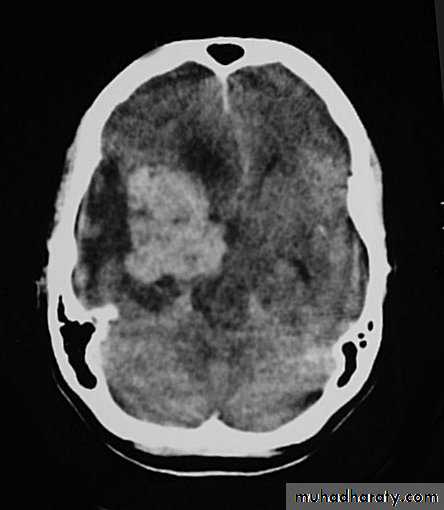

Malignant GliomaPre contrast CT

Neurosurgery

Malignant Glioma Post contrast CT